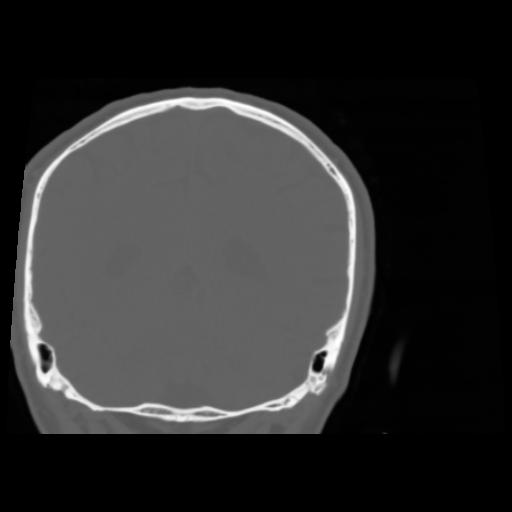

5 CEREBRO,,Coronal,3.000,CEREBRO,Coronal,